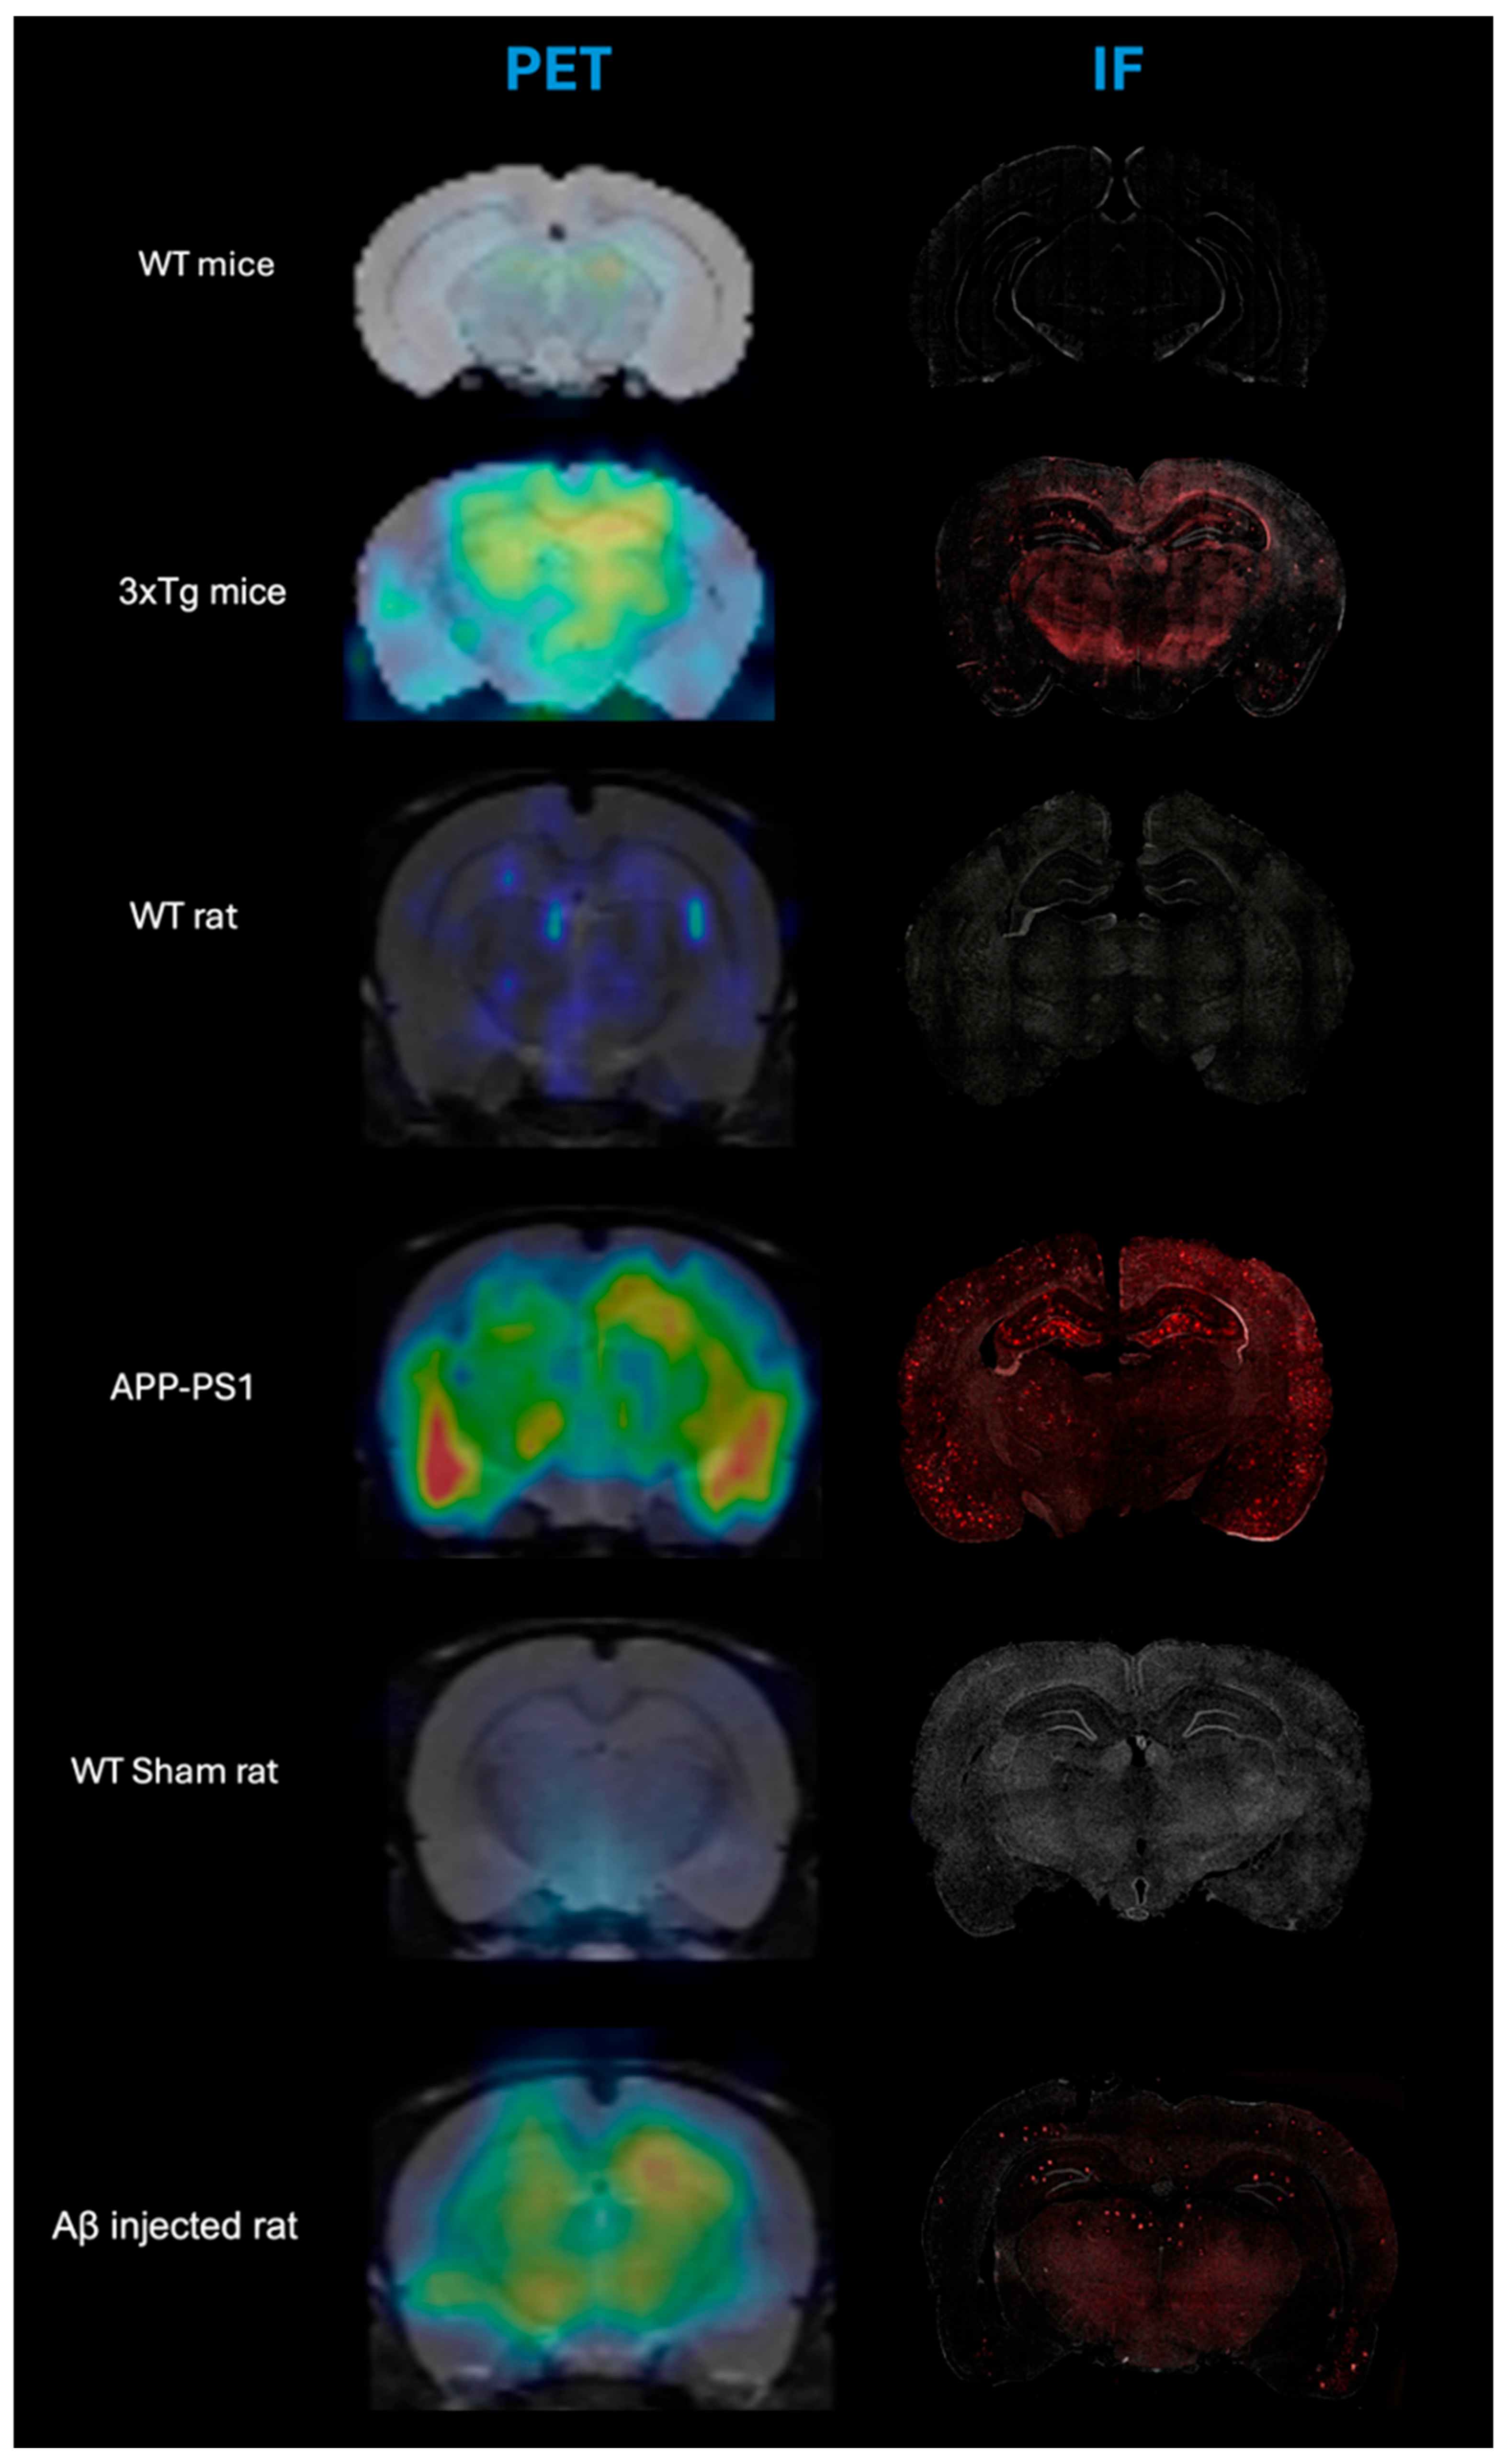

Illustrative comparison between microPET and Immunofluorescence images for the evaluated animal models and their controls are shown in Figure 1, which confirms the presence of βA plaque deposition in the evaluated animal models, and its absence in the brain of control animals.

Figure 1.

Comparative [11C]PIB PET/MRI and immunofluorescence (IF) images of coronal slices of the evaluated animal models and their controls. For microPET images, warm colors mean high uptake of [11C]PIB while in the IF, the red dots are the accumulation of amyloid plaque detected in the tissue.

In all animal models of Alzheimer’s disease evaluated in this research, the IF images showed antibody labeling in regions that also showed signal in the PET images. This match confirms the presence of Aβ deposits in the animals included in this study with AD model and highlights the added value of microPET imaging as a sensitive in vivo technique for the specific detection of Aβ deposits using [11C]PIB.